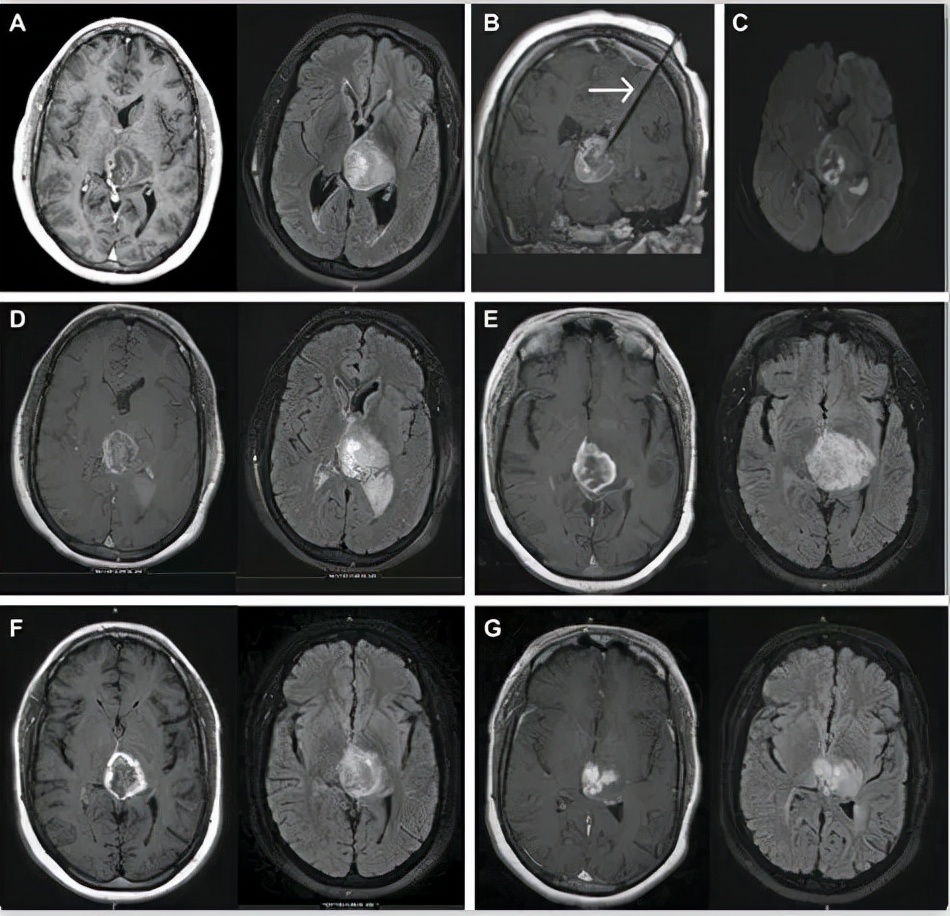

高级别胶质瘤MRI影像

一、对肿瘤病灶的表述: 对于具体的病灶,RANO标准要求必须包括对强化病灶和非强化病灶的系列评估。与Macdonald标准相同,RANO标准也是以二维评判标准进行治疗反应的评估。对于增强病灶,采用最大横截面下两垂直直径的乘积来界定肿瘤的大小,多病灶时取乘积之和,并以此作为基线。

二、影像学评价: 评定原则为在确认治疗反应前,需进行治疗前、后的影像学对比。在影像学上病灶的变化较为模糊,不足以鉴别病情稳定或进展时,允许继续治疗并观察一段时间(例如4周)。若随后的MRI检查表明出现疾病进展,则病情进展日期应为首次发现病灶变化的扫描时间。对于应用影响血管通透*药性**物的患者,评判其影像学反应尤为困难,应于4周后再次扫描以确认治疗有效或疾病稳定。对于所有的可测量病灶和非可测量病灶,应尽可能使用相同的技术参数扫描,理想情况下应采用同一台MRI仪检查,至少应具有相同的磁场强度,以减少误判。

4、病灶的测量: 对比轴位、矢状位和冠状位上各个病灶增强扫描下的截面,选取其中最大的1个病灶截面,通常为轴位下最大截面。测量最大截面下病灶的垂直直径,取两垂直直径的乘积。对多个增强病灶进行评估时,将这些病灶最大截面的垂直直径的乘积相加后,参照RANO标准进行治疗反应评估。需注意的是,在进行疗效评估时以基线期为参考,因此在进行增强MRI扫描时,应要求影像科医生遵照标准的操作流程,尽量使用同一仪器和同一扫描条件。